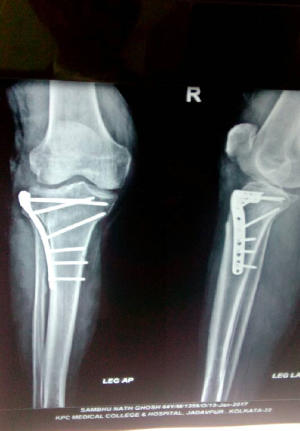

Reduction and internal fixation for proximal tibial fracture

before operation

After operation